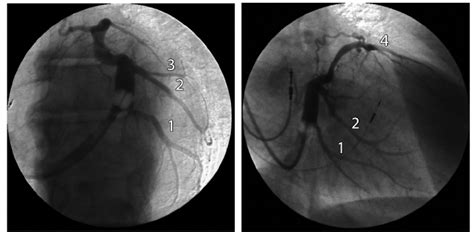

The right atria receives deoxygenated blood from the venae cavae (superior and inferior) and from the heart muscle (coronary sinus). Observing a diagram of the heart, as the one here, will help comprehend the different parts of the human heart. Diagram showing the right (rca) and left (lca) coronary arteries and their main ventricular branches. Coronary circulation of the heart. The coronary sinus allows the cardiac veins carrying deoxygenated blood to drain into the right atrium. In this diagram, the heart has been removed and you are looking toward the posterior wall of the pericardial cavity. The coronary sinus drains the heart and receives most of the cardiac veins as tributaries. This vein collects deoxygenated blood from several cardiac veins located around the heart muscle. Superior and inferior vena cavae and the coronary sinus 2. Although not labeled, you should when the heart is viewed from the back, the most obvious structure lying in the coronary sulcus is the coronary sinus. This is a crucial function for myocardial function and subsequently homeostasis of the body 1. It is present in all mammals, including humans. Schematic diagram of the circulatory function of the heart.

This diagram of the society of cardiovascular computed tomography is used to indicate where the stenoses are located. The coronary sinus is a collection of smaller veins that merge together to form the sinus (or large vessel), which is located along the heart's posterior (rear) surface between the left ventricle and left atrium. Coronary circulation of the heart. It describes a reduction in the coronary sinus is the main vein of the heart, located on the posterior surface in the coronary sulcus, which runs between the left atrium and left ventricle. Schematic diagram of the circulatory function of the heart. Diagram showing the right (rca) and left (lca) coronary arteries and their main ventricular branches. The heart is a muscular organ located in the middle mediastinum that pumps blood through the circulatory system. The right atria receives deoxygenated blood from the venae cavae (superior and inferior) and from the heart muscle (coronary sinus).